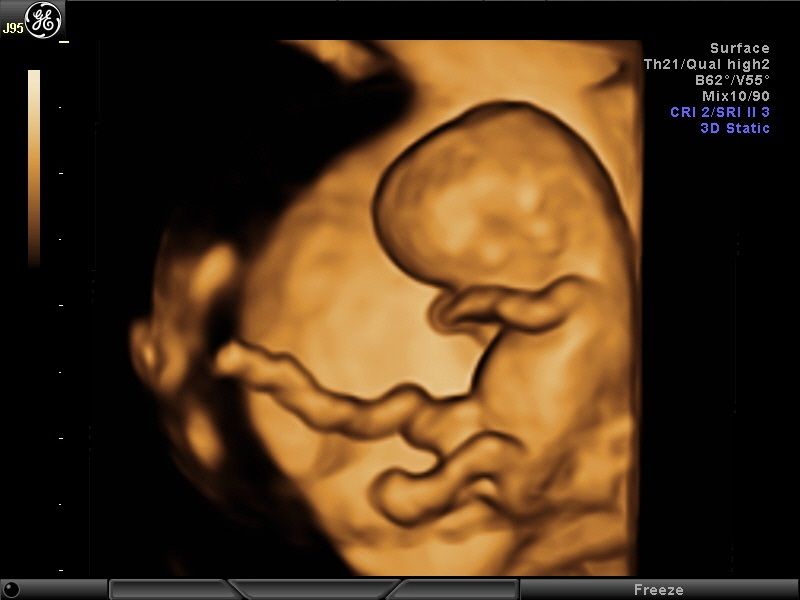

Wykonuję tam około 600 badań „I trymestru ciąży” rocznie, co daje łącznie około 1200 badań z „II trymestrem ciąży” włącznie. Od 15 lat w swoim gabinecie również wykonuję badania prenatalne I, II i III trymestru ciąży w znacznej ilości. To umożliwia mi osiągnięcie doskonałych wyników w diagnostyce tych badań, co stawia mnie w czołówce specjalistów diagnostyki prenatalnej.

Większość swojej kariery zawodowej spędziłem na sali porodowej oraz patologii ciąży. Aktualnie pracuję na sali porodowej. Mam 15-letnie doświadczenie w diagnostyce prenatalnej poparte dużą ilością przebadanych pacjentek i posiadam najszerszy wachlarz certyfikatów z zakresu ultrasonografii płodowej. Corocznie uczestniczę w szkoleniach i kursach ultrasonograficznych.

- diagnostyka prenatalna I,II i III trymestru ciąży z przepływami dopplerowskimi, testem podwójnym (PAPPA i B-HCG), oznaczanie DNA płodowego NIPTY, testy SANCO, NIFTY, VERACITY